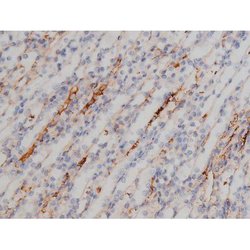

Invitrogen™ Phospho-NPM1 (Thr199) Polyclonal Antibody

Antibody detects endogenous levels of Nucleophosmin only when phosphorylated at Threonine 199.

| Applications | Immunohistochemistry (Paraffin), Western Blot, Immunocytochemistry |